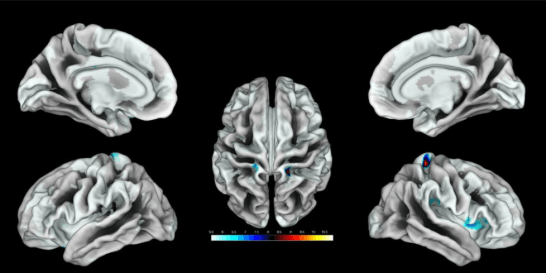

Ahora, una investigación realizada por expertos de varias instituciones alemanas y publicada esta semana en The Journal of Neuroscience sostiene que la representación de los genitales en el mapa cerebral está cerca de la representación de la cadera si bien hay que localizarlo individualmente ya que la ubicación precisa varía “probablemente” entre ellas.

“Nuestro enfoque de mapeo produjo activaciones corticales en la pared lateral de la corteza somatosensorial para todas las mujeres, aunque la localización precisa cambió de mujer a mujer”, explica a SINC Christine Heim, profesora de la Universidad Charité de Berlín (Alemania) y autora principal.

El trabajo también descubrió que la región era más gruesa cuanto más frecuentemente mantenían relaciones sexuales las participantes. “Nunca se había demostrado en humanos que este campo de representación genital tuviera la capacidad de variar estructuralmente en relación con su uso”, añade.

“Nuestro enfoque de mapeo individual proporcionó una mayor precisión que en investigaciones anteriores y localizó inequívocamente el campo genital”, continúa Heim, que recogió una muestra de 20 mujeres.

Variabilidad interindividual de la corteza somatosensorial genital. / Knop et al., JNeurosci 2021